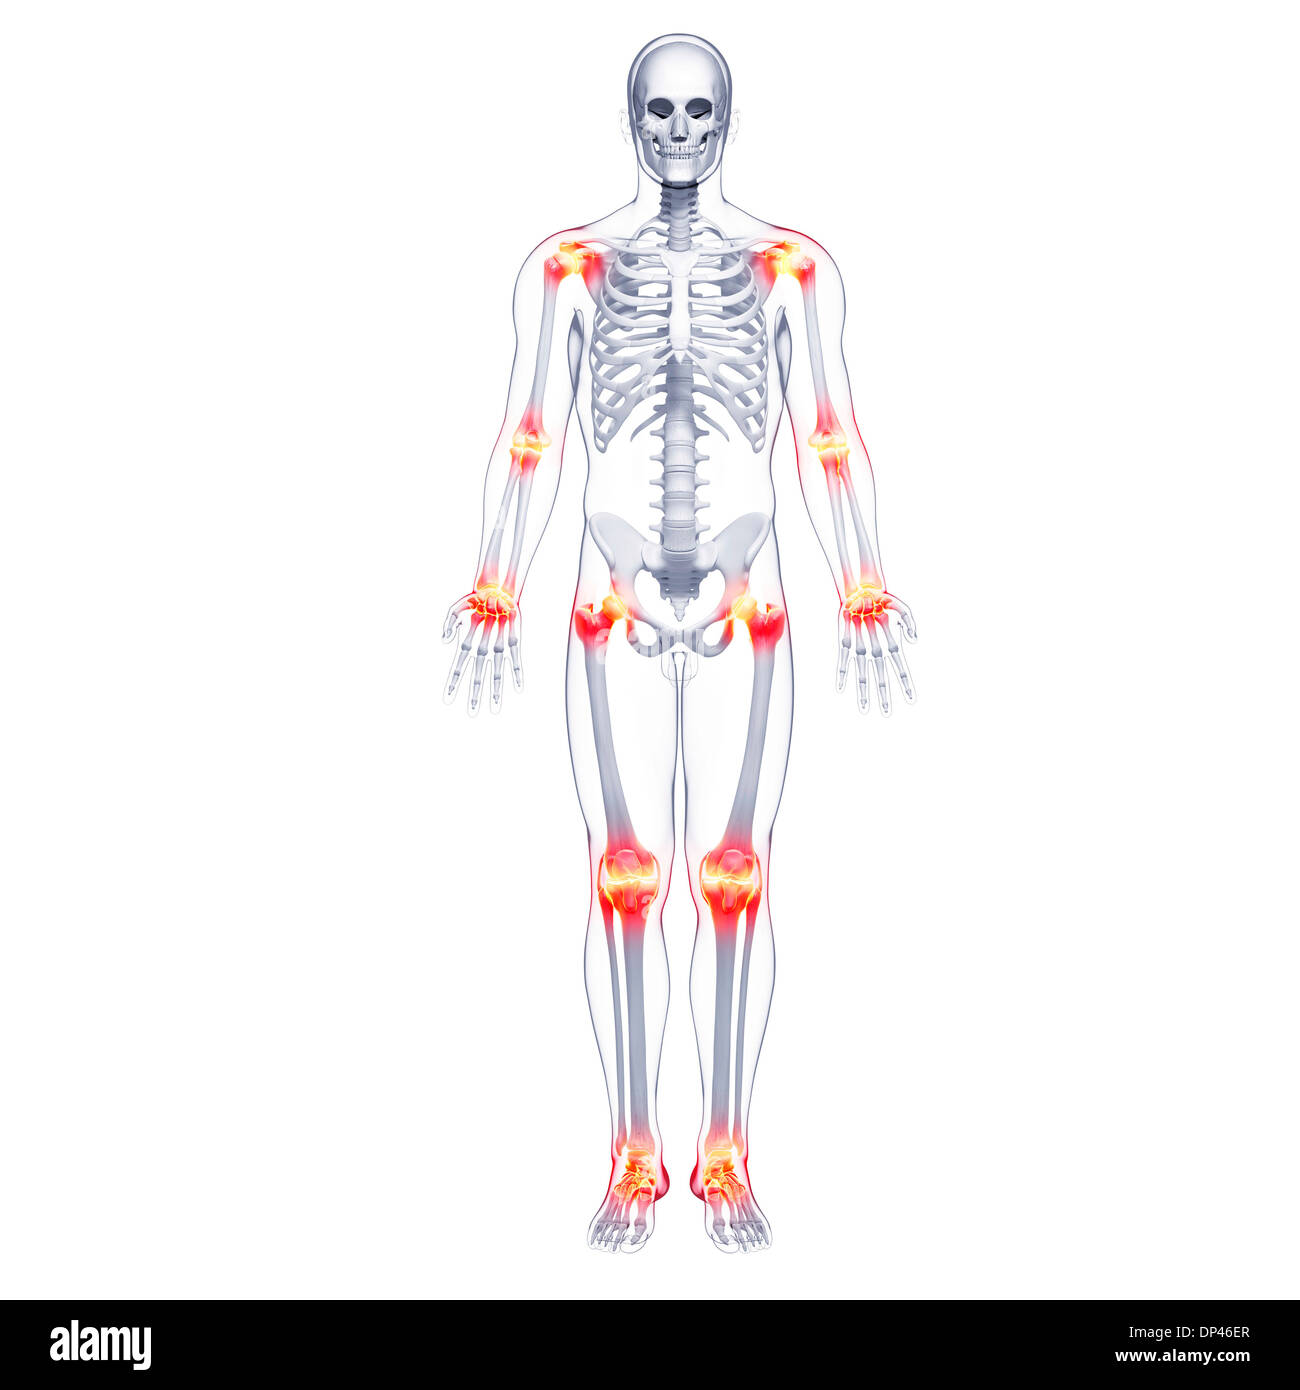

La douleur commune, artwork Banque D'Imageshttps://www.alamyimages.fr/image-license-details/?v=1https://www.alamyimages.fr/la-douleur-commune-artwork-image65205748.html

La douleur commune, artwork Banque D'Imageshttps://www.alamyimages.fr/image-license-details/?v=1https://www.alamyimages.fr/la-douleur-commune-artwork-image65205748.htmlRFDP2AGM–La douleur commune, artwork